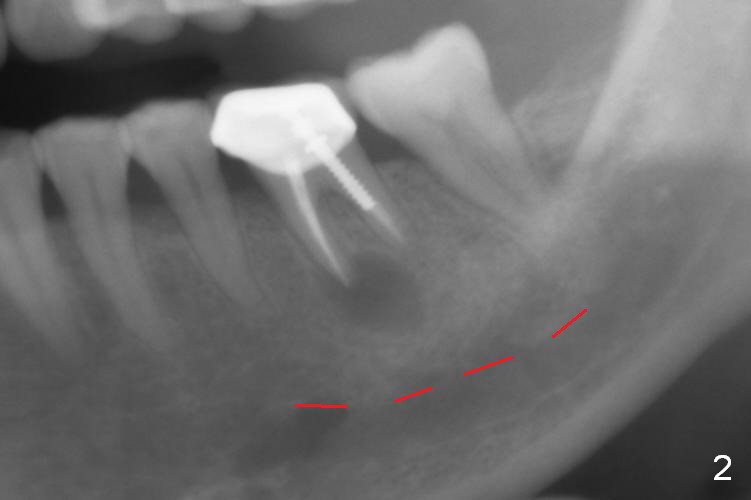

A 58-year-old lady has a long-standing periapical lesion with several episodes of acute infection (Fig.1-3, taken 10, 9 and 2 years ago, respectively). Explore the socket for size and wall integrity (Clindamycin). If the bony defect is not extensive, place a longest implant (18 mm bone-level, 20 mm tissue-level) with moderate diameter (5.5, 6 mm). Otherwise use a shorter, but wider tapered implant (7x12 mm (bone-level), 7 or 8x17 mm (tissue-level)). If the socket is extremely large, consider using 7 or 8 x20 mm cylindrical tissue-level implant. Use Bicon 2 mm pilot drill with extension to measure the socket depth and obtain 3-6 mm new bone or until 20 mm (gingival margin). Take PA. The 1st option is to use UF 3-4.7x18 mm drills at 50 RPM. Make sure that the depth is reached (septum crestal level) and check osteotomy wall integrity after each drill. Then place a 5 or 5.5x16 or 18 mm implant (Fig.6). The 2nd and 3rd options are shown in Fig.4 and 5. Due to severe infection and pain, a shorter implant is placed.